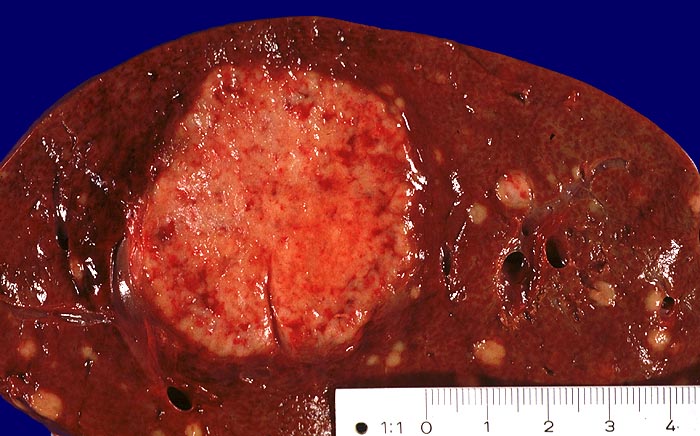

AP/ Lebermetastase: Neuroendokrines Karzinom

Lebermetastase: Neuroendokrines Karzinom

Leber

Makroskopie